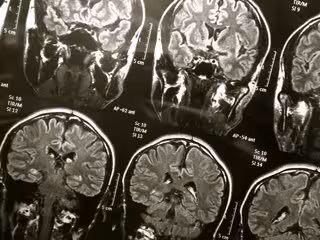

FLICKR/WYINOUE - Archivo